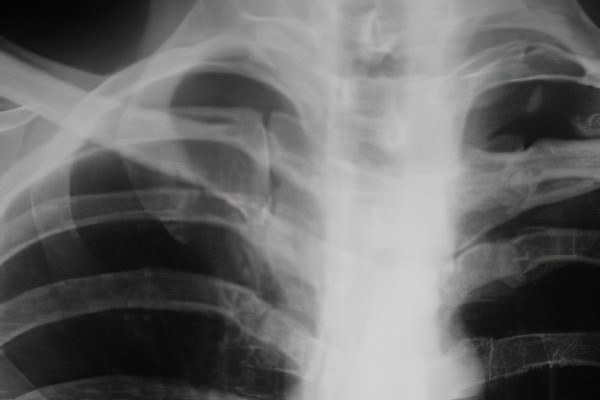

Перелом первого ребра является серьезной травмой, которая требует внимательного подхода со стороны медицинских специалистов. Врачи отмечают, что такая травма часто сопровождается повреждением окружающих мягких тканей и может привести к осложнениям, включая пневмоторакс или повреждение сосудов. Важно, чтобы пациенты с подозрением на перелом первого ребра проходили тщательное обследование, включая рентгенографию или компьютерную томографию.

В современной медицине для диагностики переломов ребер используются рентгенография, магнитно-резонансная томография (МРТ) и компьютерная томография (КТ). Сначала выполняется рентгеновский снимок, который часто достаточно для выявления очевидных и простых переломов. Если рентген не дает четкой картины или не позволяет определить степень и местоположение повреждения, рекомендуется использовать МРТ и КТ. Эти методы помогают точно установить характер травм как ребер, так и окружающих мягких тканей и сосудов.